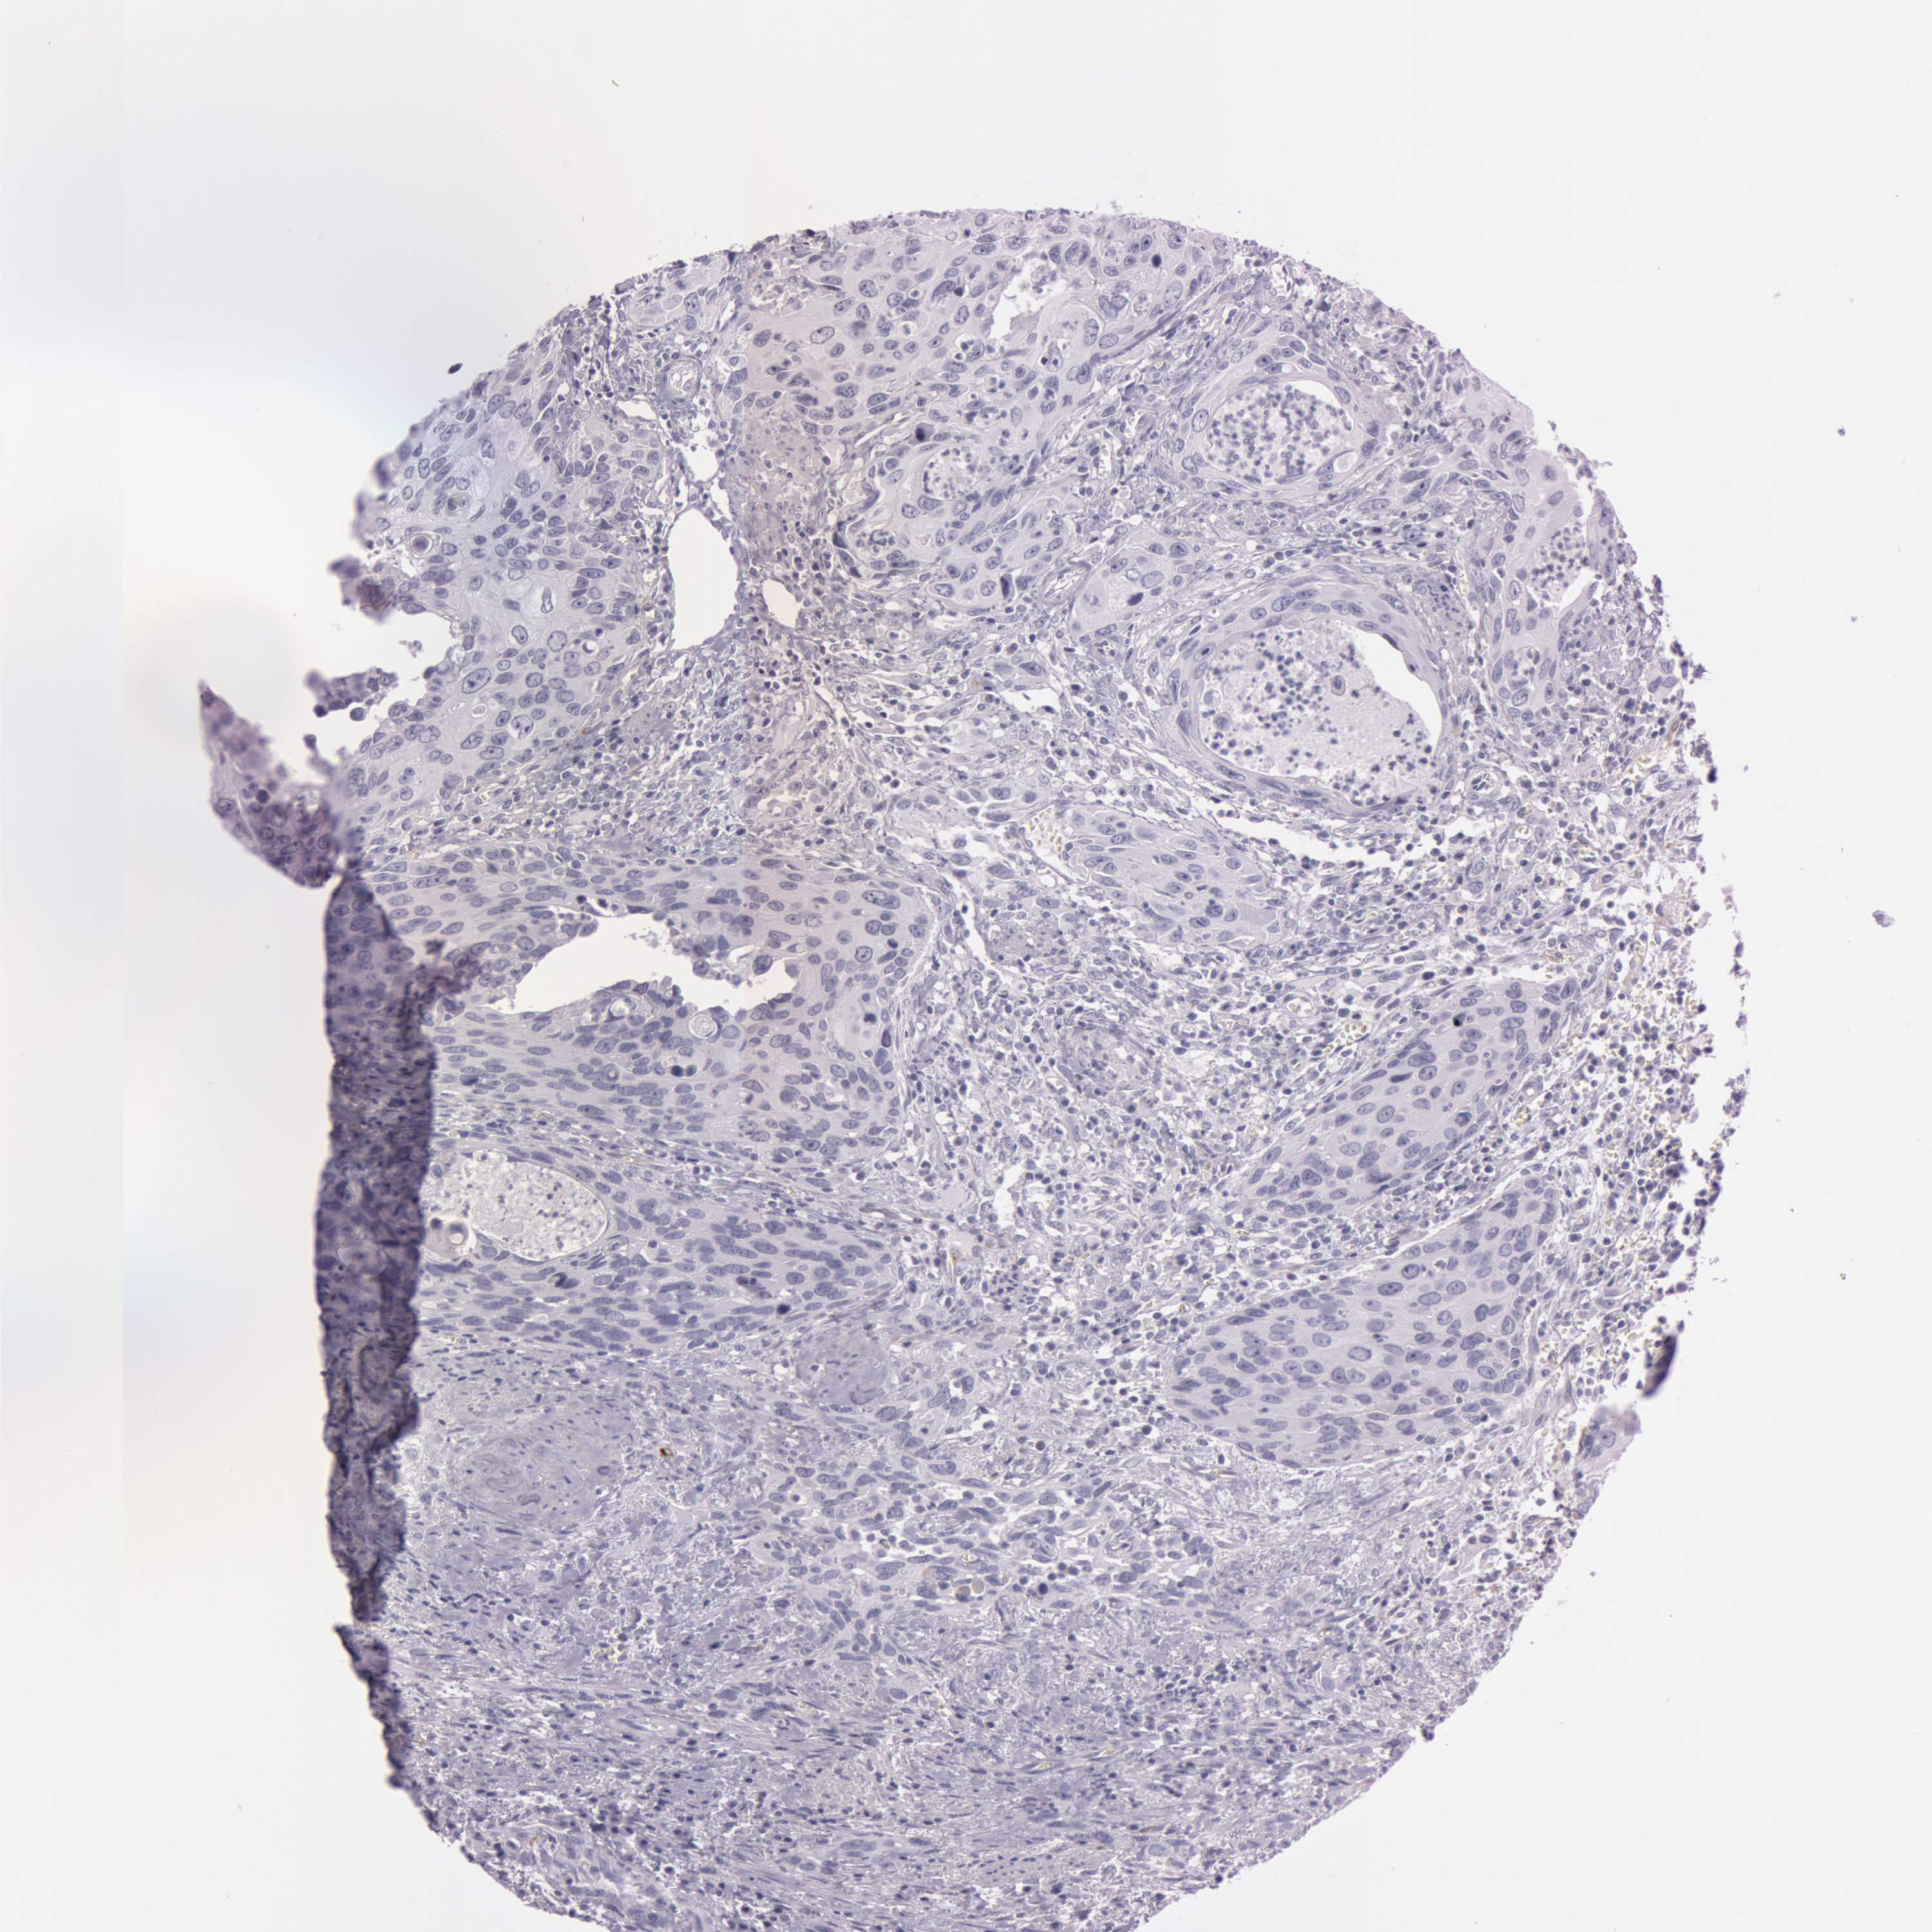

UROTHELIAL CANCER - Protein expressioni

A mouse-over function shows sample information and annotation data. Click on an image to view it in a full screen mode. Samples can be filtered based on level of antibody staining by selecting one or several of the following categories: high, medium, low and not detected. The assay and annotation is described here.

Note that samples used for immunohistochemistry by the Human Protein Atlas do not correspond to samples in the TCGA dataset.

Antibody stainingi

Antibody staining in the annotated cell types in the current human tissue is reported as not detected, low, medium, or high, based on conventional immunohistochemistry profiling in selected tissues. This score is based on the combination of the staining intensity and fraction of stained cells.

Each image is clickable and will lead to virtual microscopy that enables deeper exploration of all samples and also displays staining intensity scores, fraction scores and subcellular localization as well as patient and tissue information for each sample.

Antibody HPA010593

Antibody CAB001451

Staining

High

Medium

Low

Not detected

Intensity

Strong

Moderate

Weak

Negative

Quantity

>75%

75%-25%

<25%

None

Location

Nuclear

Cytoplasmic/membranous

Cytoplasmic/membranous,nuclear

Urothelial carcinoma, Low grade

Urothelial carcinoma, High grade

Adenocarcinoma, NOS